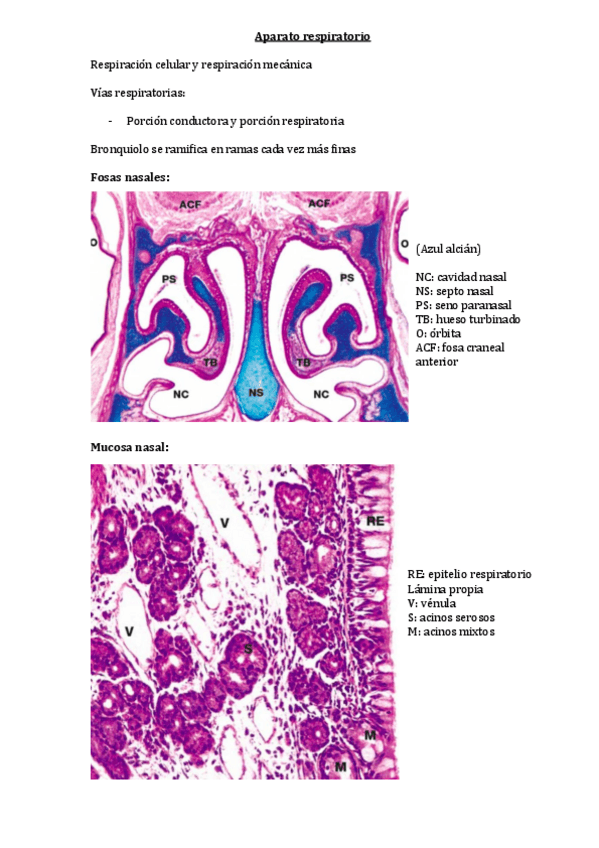

BLOQUE II - Respiratorio

He publicado nuevos apuntes de 2º Histología Médica Especial: BLOQUE II - Respiratorio

TEMA-1.-Cavidad-nasal-faringe-laringe-y-traquea.pdf

TEMA-2.-Pulmon.pdf

TEMA-3.-Alveolos-y-pleura.pdf